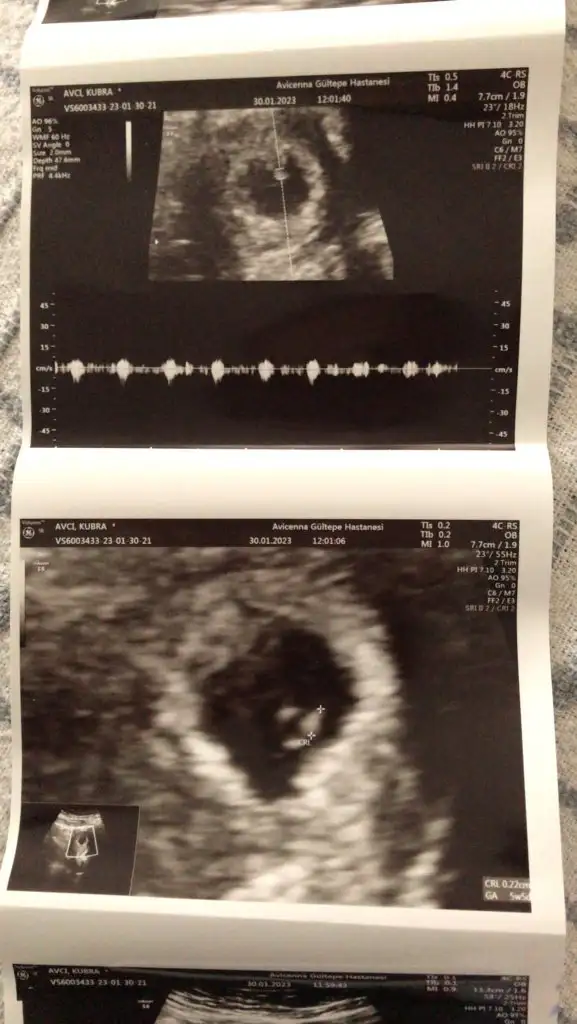

• IMG-20230130-WA0001.webp

IMG-20230130-WA0001.webp

37,1 KB · Görüntüleme: 95

• IMG-20230130-WA0002.webp

IMG-20230130-WA0002.webp

32,2 KB · Görüntüleme: 91